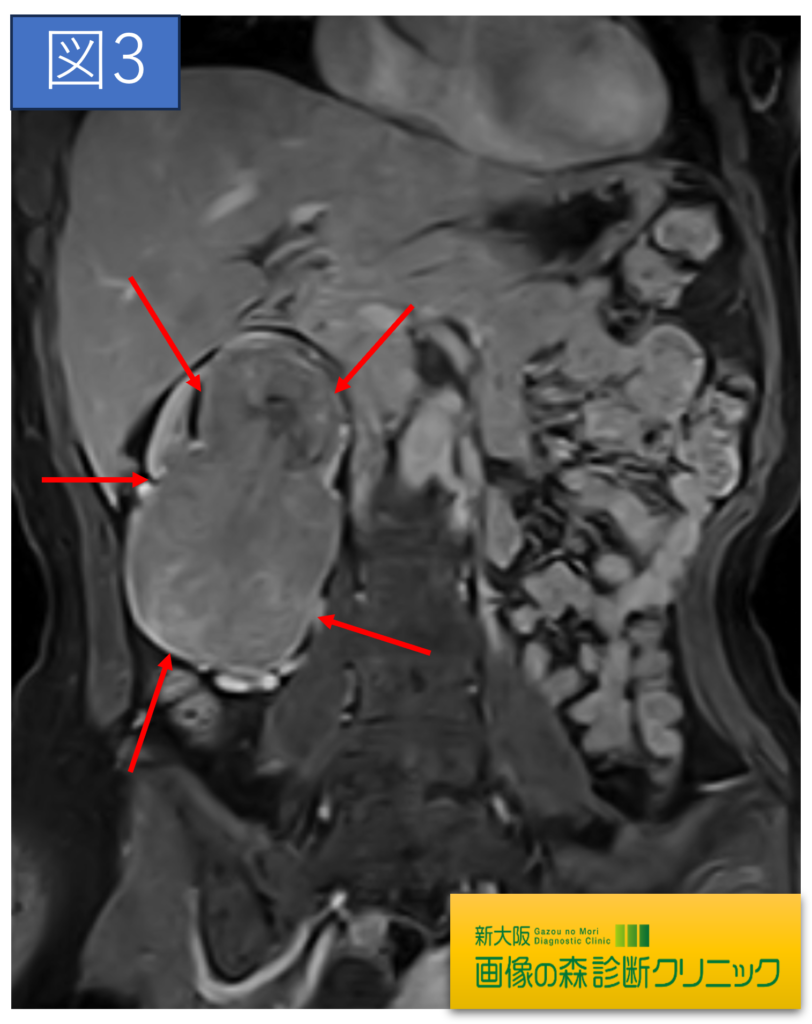

腎臓造影MRI画像(冠状断像)

症例画像から図1~図4は腎臓癌の画像です。矢印は腎臓癌を示します。図1・図2はDWIBS_MRIの画像です。DWIBS_MRIは、頚部~骨盤までの広範囲の癌検索を目的としており、癌の疑いのある臓器はこの画像の場合、黒く描出されます。(脳や脾臓も黒く見えますが、これらの部位は他の部位より黒く描出されやすいので、その他の撮影画像と比較することで評価されます)図3・図4は造影剤を使用し腎臓に焦点をあて検査した画像です。